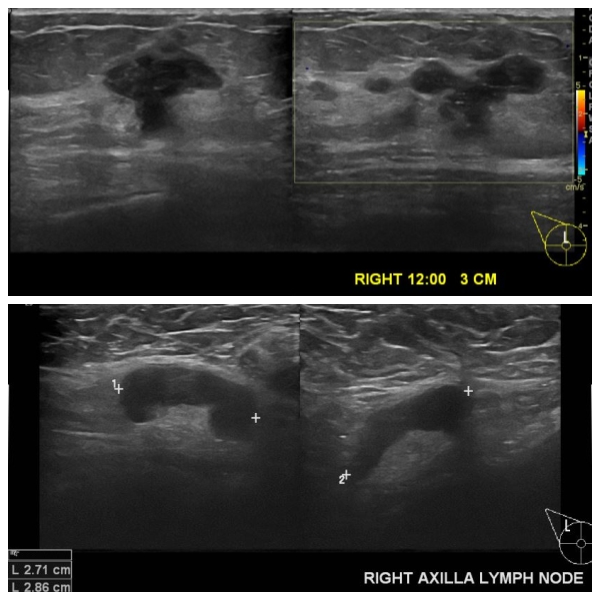

상기환자 우측 만져지는 멍우리로 내원하신 50대 여성 분으로 우측 12시 방향에서 3cm

떨어진 거리의 만져지는 혹 조직검사 시행하여 우측 침윤성 유관암 진단 되었으면, 우측

겨드랑이 림프절 비대 세포검사 시행하여 전이암으로 진단 되었습니다.